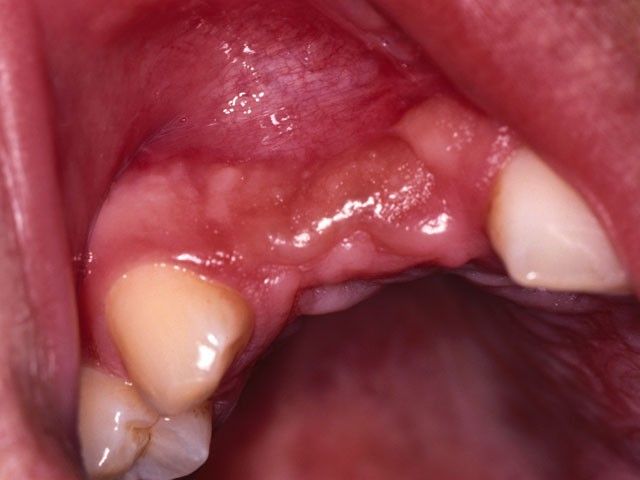

Από το 1992, ο χειρουργός οδοντίατρος Ιωάννης Μαρινάκης, στα Χανιά, ασχολήθηκε με τη χειρουργική τοποθέτηση εμφυτευμάτων και αναπλαστικών υλικών ιστικής και οστικής αναγέννησης.

Τη δεκαετία του 1990 αναπτύχθηκαν μέθοδοι με τις οποίες μπορούμε να επιτύχουμε μερική ανάπλαση των ιστών που συγκρατούν τα δόντια (περιοδόντιο) και μεγαλύτερη έως πλήρη ανάπλαση του φατνιακού οστού. Καθοριστικής σημασίας ήταν, αρχικά, η χρήση της ημιδιαπερατής μεμβράνης και στη συνέχεια των αυξητικών παραγόντων, προϊόντων υψηλής βιοτεχνολογίας.

Το περιστατικό στις φωτογραφίες είναι του 1998 και αφορά αποκατάσταση απώλειας δοντιών και οστού στην πρόσθια άνω περιοχή από τροχαίο ατύχημα: